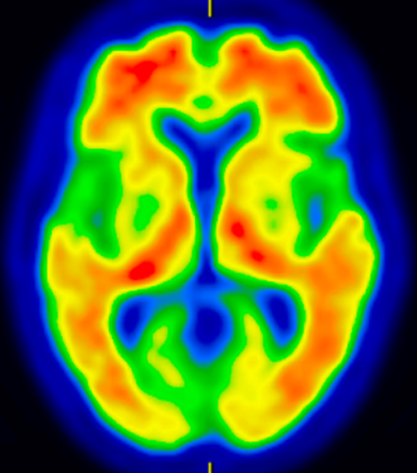

* 脳血流SPECT(図1):それぞれの認知症に特徴的な血流低下所見を確認して、鑑別診断の精度を高めます。

* アミロイドPET(図2):当院で実施可能です。アルツハイマー病の原因物質と考えられているアミロイドβプラークが、脳内に溜まっているかどうかを調べる検査です。抗アミロイドβ抗体薬を使用するには、アミロイドPETが陽性である必要があります。

図1 アルツハイマー型認知症の脳血流SPECT

図2 アルツハイマー型認知症のアミロイドPET